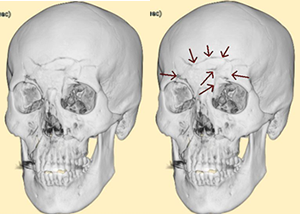

CTは前頭葉左側部の頭蓋骨骨折と脳挫傷の合併症です。対側損傷が発生し、対角線上の右後頭部に脳挫傷を発症しています。